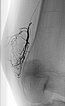

In gleicher Sitzung erfolgt dann noch eine Sklerosierungstherapie in Direktpunktionstechnik. Unter Ultraschallsteuerung wird die venöse Malformation anpunktiert und Kontrastmittel injiziert.

Es kontrastiert sich unmittelbar eine drainierende Vene, die in die Vena femoralis abfließt und damit mit dem tiefen Leitvenensystem kommuniziert. Diese wird mit Alkoholgel verschlossen.